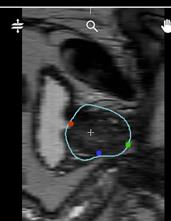

Comment le constater : Au moment de l'affichage du volume DICOM en page "Contour", le volume est affiché inversé sur l'axe apex-base. La position de la vessie est un point de repère efficace : "à gauche", le volume est affiché correctement, "à droite", le volume est affiché inversé.

| Image affiché correctement : la vessie est à gauche | Image affichée inversée : la vessie est à droite |